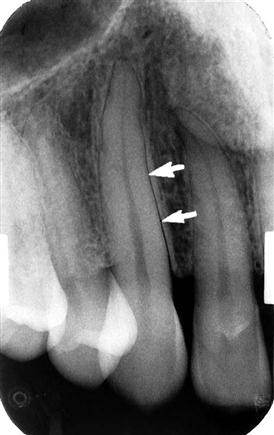

horizontal bone loss

most common in periodontitis

fairly even reduction in the height of the alveolar bone

vertical bone loss (angular bone loss)

less common

uneven reduction in the height of the alveolar bone